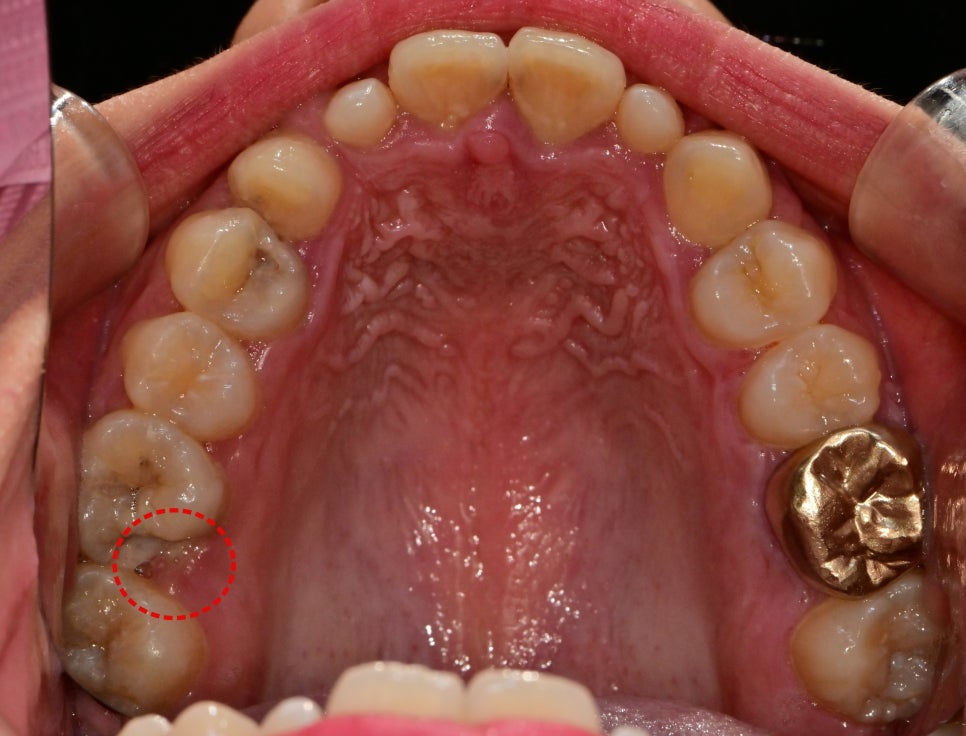

충치로 인해 깨진 치아 부위에 잇몸이 차올라 있는 경우

마지막으로 소아에서 일어나는 케이스는 아니지만

충치가 생긴지 오래되고 치아가 깨진 치아에서

자주 볼 수 있는 현상으로

해당 부위의 충치가 심해서 치아가 깨져있는 부분으로

잇몸이 차올라서 치아머리 부분을 확보할 수 없었습니다.

주변 플라그에 의해 일시적으로 비대해져 있는 잇몸은

스케일링 후 회복이 되면 정상 높이로 회복이 되지만

잇몸이 증식된 경우 충치치료를 하고

증식되어 있는 부분의 잇몸을 절제해야지만

크라운치료시 제대로 된 적합을 만들 수가 있습니다.